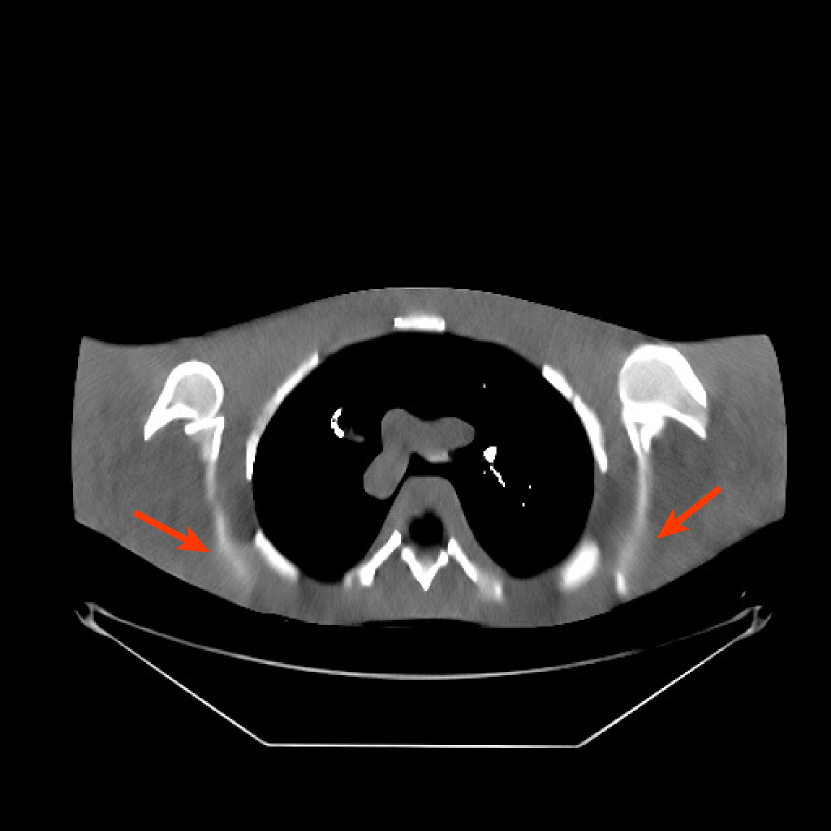

We obtained from GE a 2D fan-beam raw (pre-log) scan of a shoulder phantom, which included the beam-hardening effect. The provided 200mA200mA200~{}\text{mA} with 1 second scan can be viewed as a standard-dose scan and all the raw measurements are positive. Based on this standard-dose scan, we simulated an ultra low-dose scan as shown in (15) with α=200𝛼200\alpha=200, and added Poisson and Gaussian noise (σ=5𝜎5\sigma=5) to the measurements. The simulated measurements have about 0.4%percent0.40.4\% non-positive values. The sinograms were of size 888×984888984{888\times 984}, and reconstructed images were of size 512×512512512{512\times 512} with Δx=Δy=0.9766subscriptΔ𝑥subscriptΔ𝑦0.9766{\Delta_{x}=\Delta_{y}=0.9766} mm.

Refer to caption

Figure 10: Reconstructions for ultra low-dose 2D scan simulated from raw measurements. The leftmost image is the PWLS-EP reconstructed image for the 200 mA200 mA200\text{ mA} scan. The second image is the PWLS-EP reconstruction for the simulated ultra low-dose scan, and it is the initial image for WavResNet [46], PWLS-ULTRA [38], and SPULTRA. The display windows are [800, 1400] HU.

Fig. 10 shows the reconstructions for the 200 mA200 mA200\text{ mA} scan (reference image) along with the reconstructions for the simulated ultra low-dose scan obtained with PWLS-EP, WavResNet, PWLS-ULTRA, and SPULTRA. Visually, WavResNet fails to reconstruct the image but improves over the initial PWLS-EP reconstruction, while PWLS-ULTRA and SPULTRA provide better image quality. This indicates that the ULTRA-based methods may have a better generalization property than WavResNet, since they learn more fundamental features of CT images (also see [38]). We selected three smooth ROIs, where the pixel values are approximately constant. Tab. V(b) shows the mean and the standard deviation of pixel values for these ROIs for various methods and the standard-dose reference. Since the iterative RNN version of WavResNet only has small improvements over PWLS-EP, the pixel values do not change much compared with PWLS-EP. PWLS-ULTRA however reduces the bias in the central region of the image (ROI 2), but fails to correct the bias in the regions near the bones (ROI 1 and ROI 3). SPULTRA reduces the bias in the central region of the image, and also significantly corrects the bias near the bone regions. The standard deviations of the ROIs reconstructed by SPULTRA are comparable to those reconstructed by PWLS-ULTRA, and are close to those of the reference ROIs. Additionally, SPULTRA reconstructs the bone (indicated by the magenta arrow in the last two subfigures of Fig. 10) better than PWLS-ULTRA.